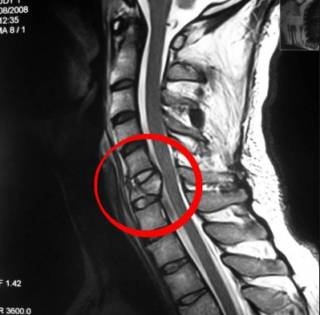

Грыжа, выявленная при диагностике с помощью КТ

Если у человека при каждом прогибе хрустит позвоночник, следует обратиться к врачу и пройти осмотр, а затем и инструментальную диагностику:

- рентген и МРТ позвоночника – всех отделов;

- КТ.